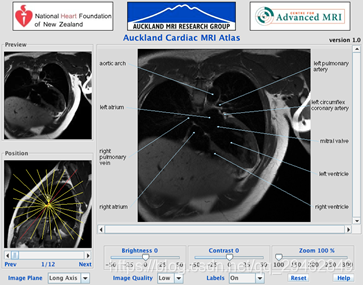

七、AMRG Cardiac Atlas(心脏MRI图像)

数据下载链接:http://www.cardiacatlas.org/studies/amrg-cardiac-atlas/

数据介绍:奥克兰MRI研究小组的Siemens Avanto扫描仪采集的正常患者心脏的完整带标签MRI图像集。